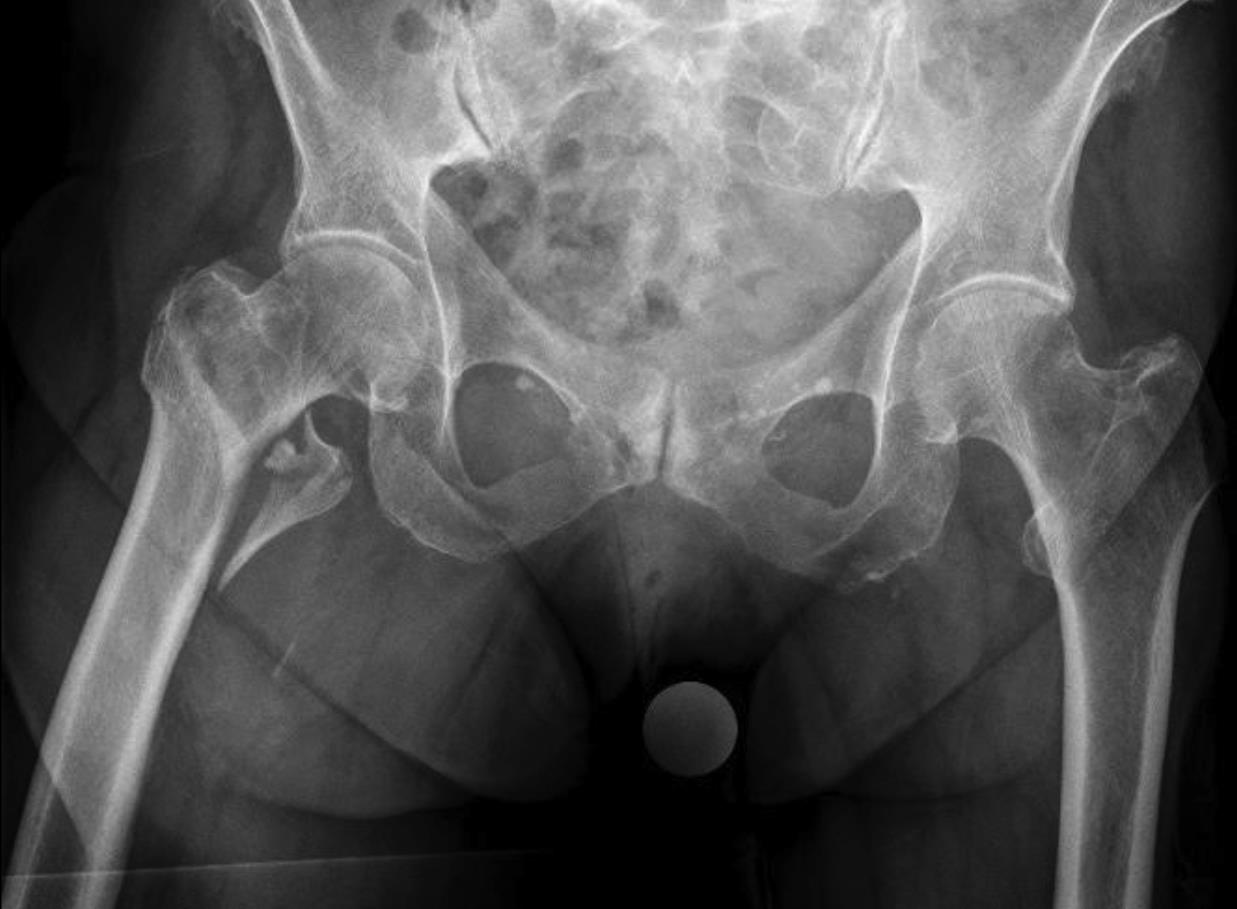

An 83-year-old female patient sustained a 31-A.2.2 fracture of the right proximal femur after a fall at home (Figs 1-2). Intraoperative and postoperative images are shown (Figs 3-5).

A 98-year-old female patient sustained a pertrochanteric fracture of the left proximal femur due to fall in her nursing home (Fig 1). There was significant pain and coxarthritis in the right hip, and hypertension. Surgery was performed within 24 hours. There was an indication for augmentation due to the instability of the fracture. The patient additionally suffered from osteoporosis and dementia.